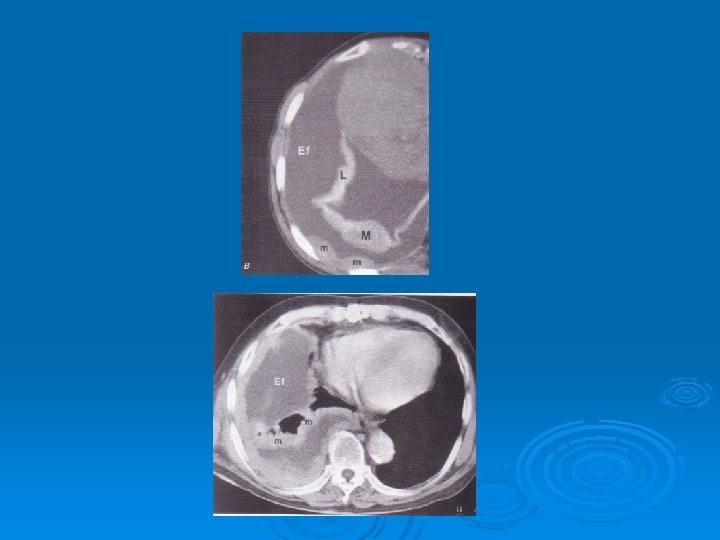

Ø The most common clinical presentations are dyspnea, chest pain, unilateral decreased volume of the affected hemithorax (frozen chest) (inspite of fluid accumilation) Ø Nodular thickening of the pleura, irregular thickening of the interlobar fissure, absence of mediastinal shift with massive pleural effusion (frozen chest) Diagnosis by histologic examination Ø Treatment oncologic and surgical if possible, prognosis is poor Ø